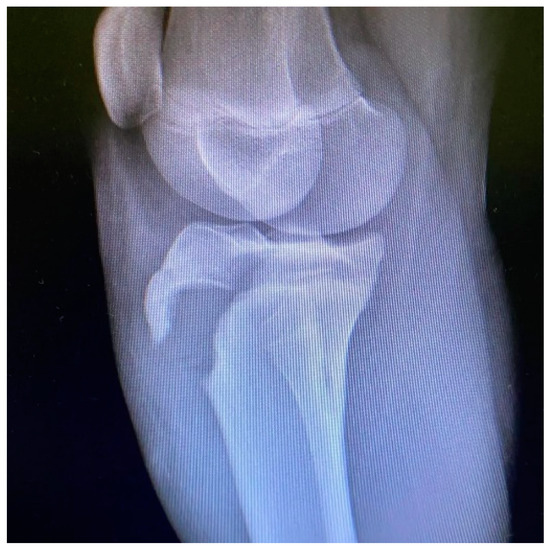

Tibial Tubercle Avulsion Fracture in Young Athletes Surgically Treated: Mid-Long Term Result and Comparison

1. Introduction